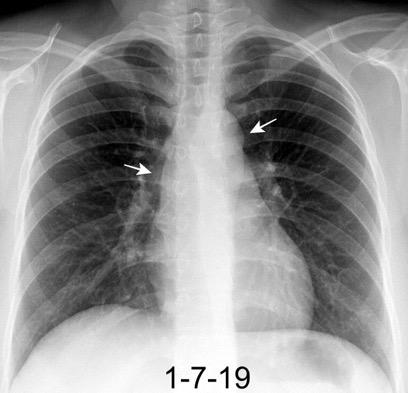

Triada de Garland

Ganglios paratraqueales derechos e hiliares bilaterales

95% de pacientes tienen ganglios hiliares bilaterales aislados o con afectación mediastínica (espec. paratraqueal derecho).

Criado E et al. Pulmonary sarcoidosis: typical and atypical manifestations at high-resolution CT with pathologic correlation. Radiographics. 2010